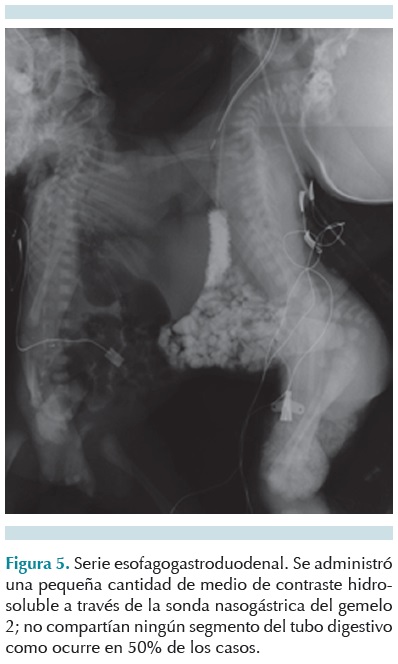

Se realizó un tamiz metabólico ampliado, ácidos orgánicos en orina. Un ultrasonido toracoabdominal (Figuras 3 y 4) mostró un ángulo de separación de la parrilla costal compartida en la cara anterior. Se observó un hígado unido por un istmo central, sin evidencia de que compartieran estructuras vasculares. Se realizó un estudio de tránsito intestinal (Figura 5).